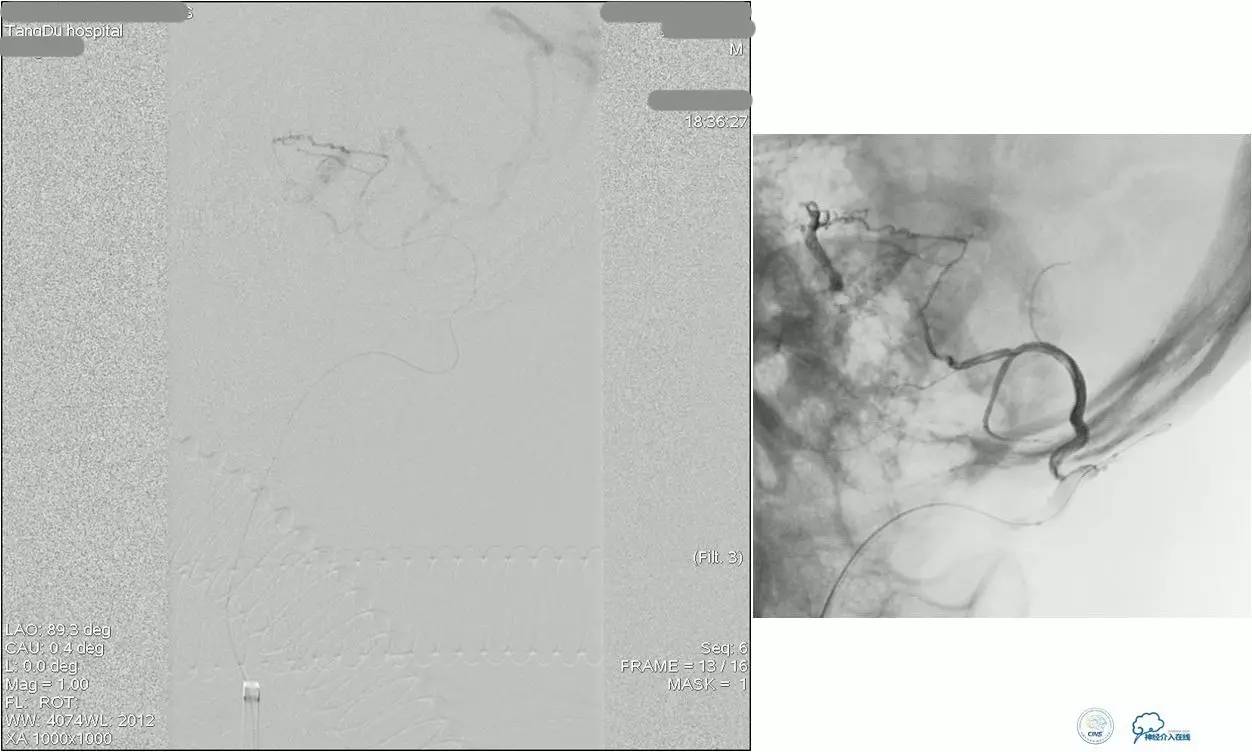

乙状窦区的DAVF,供血动脉细小,静脉引流道通畅。

同侧颈内静脉试图进入引流静脉,但是由于角度问题非常困难。

从对侧颈内静脉绕路进入引流静脉。

Sceptor球囊导管到达静脉内,充盈球囊,让后注入Onyx。

术后造影提示DAVF治愈。